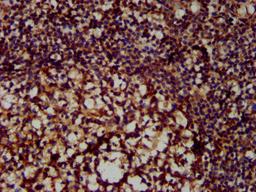

IHC image of CSB-PA015250LA01HU diluted at 1:300 and staining in paraffin-embedded human tonsil tissue performed on a Leica BondTM system. After dewaxing and hydration, antigen retrieval was mediated by high pressure in a citrate buffer (pH 6.0). Section was blocked with 10% normal goat serum 30min at RT. Then primary antibody (1% BSA) was incubated at 4°C overnight. The primary is detected by a biotinylated secondary antibody and visualized using an HRP conjugated SP system.